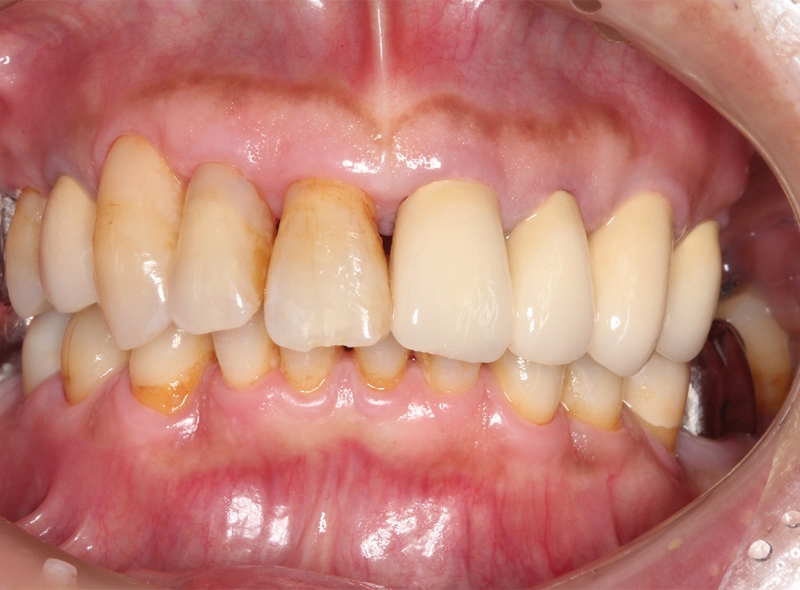

CASE 歯周病治療症例

After

| 年齢 | 59歳 |

|---|---|

| 性別 | 男性 |

| 症状 | 歯がグラグラする。歯茎が腫れる。 |

| 治療法 | 歯周病治療 補綴治療(被せ物) |

| 費用 | 症例による(基本的には保険治療で可能) |

| 通院回数 | 症例による |

| リスク・副作用 | 知覚過敏症状がでることがある |

| 備考 | 歯を支える骨が高度に吸収していたが、歯周病治療と被せ物の治療により改善し、治療完了。 |